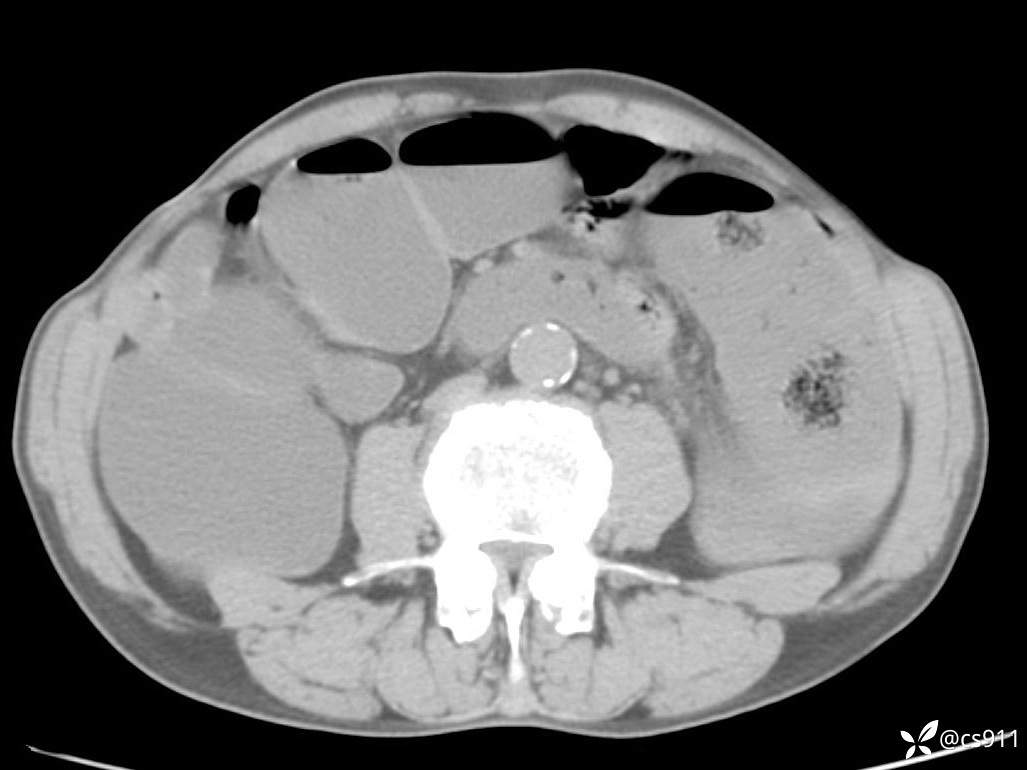

急腹症之急诊CT,原因?答案公布

男,77岁,腹痛、腹胀伴恶心呕吐1天。呕吐胃内容物,非喷射性呕吐,有咖啡色样胃内容物,诉有胃穿孔病史。查体:全腹平,下腹部压痛,全腹无反跳痛,叩诊呈浊音,移动性浊音阴性,肠鸣音减弱,1-2次/分。肛检:直肠未扪及明显肿物,可触及大量粪块。

血淀粉酶(AMY) HH 1859 U/L 35-135